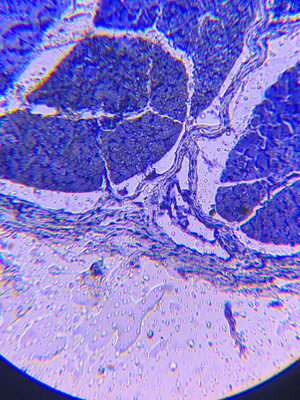

Data from Google Earth / Hirudo, sectionio transversus (Livka, cross section). Micropreparate on the optical glass

Cor rattus, sectionio longuitudinalis (heart of rats, longitudinal section). Micropreparatom on the optical glass. / Scotch on the pine. Moscow region, zoom lens, compact camera.